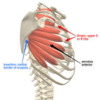

Serratus Anterior

Action: protract scapula and holds it against thoracic wall; upward rotation of scapula

Sup/prox: exterior lateral surface of ribs 1-8

-digitations on anterior side, lateral to ribs, inferior to scapula laterally

Inf/dist: anterior surface of medial border of scapula

Innervation: Long thoracic N. C5, *C6*, C7